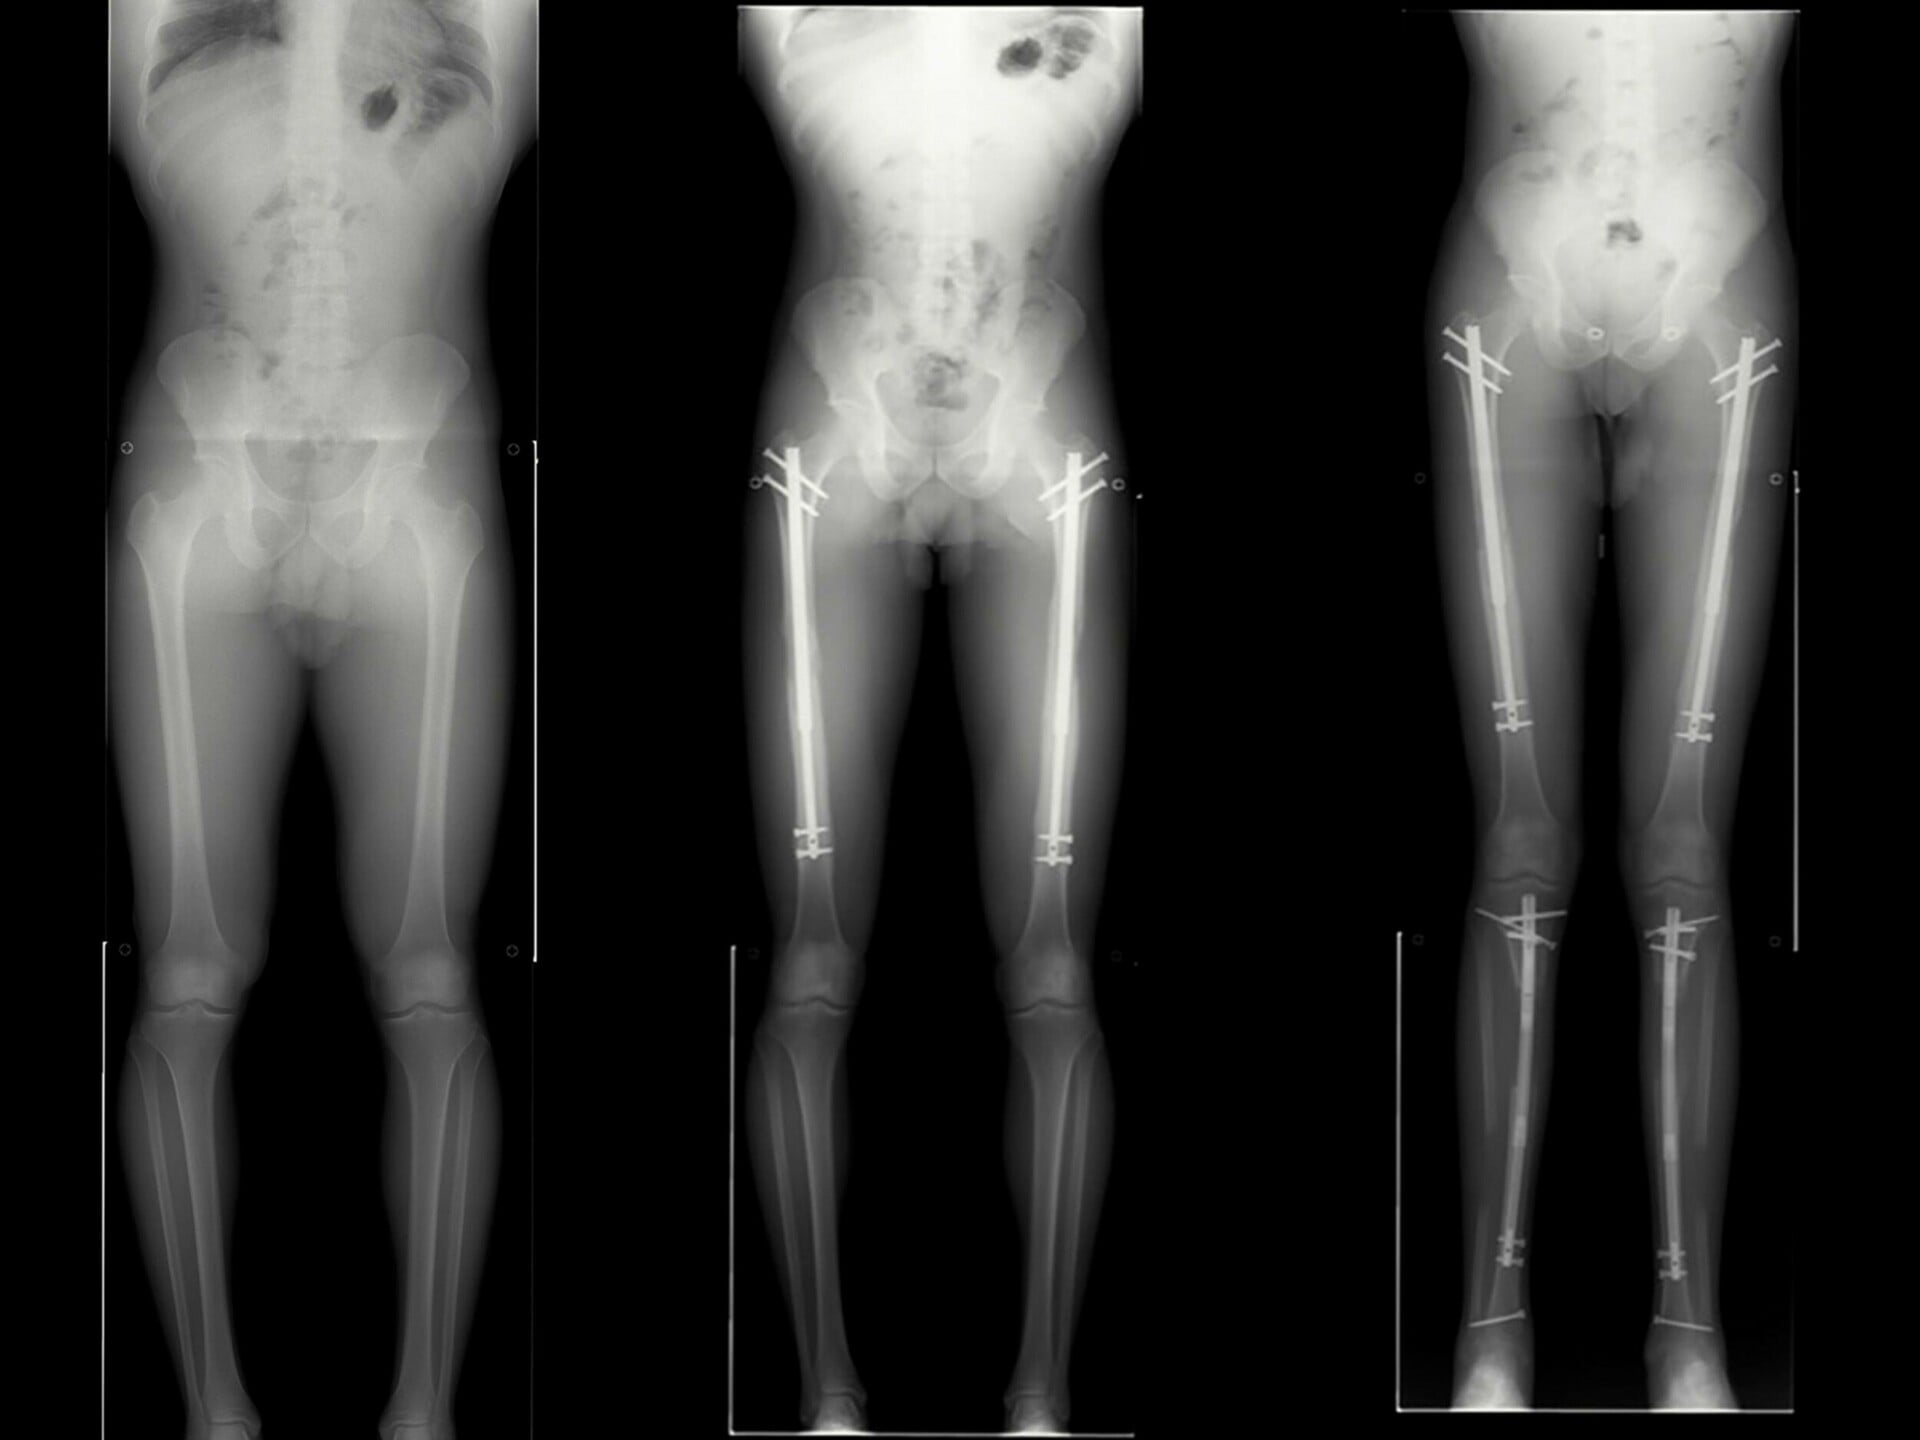

Ακτινογραφίες πριν και μετά ενός ασθενούς που είχε επιμηκύνει και τα μηριαία και τα κνήμια οστά του, αυξάνοντας το ύψος του κατά έξι ίντσες.